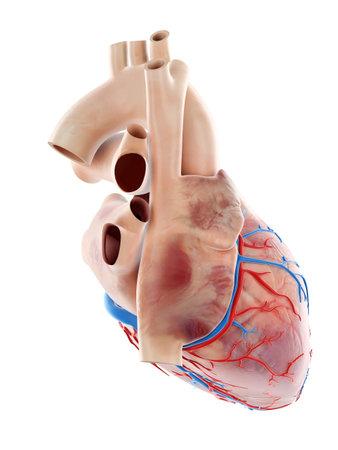

Медицинская 3D иллюстрация человеческого сердца с высокой точностью.

Анатомическая иллюстрация человеческого сердца, с ясно обозначенными венами и голубоватым оттенком, предназначенная для медицинских и научных целей.